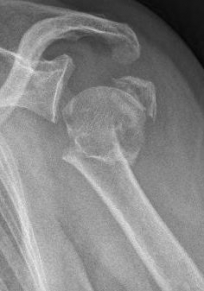

Picture: In the above pictures, a slightly shifted subcapital humeral fracture was internally splinted using intramedullary nail. The left picture is a follow-up examination half a year after the accident and shows the complete healing of the fracture with correct position of the bone.